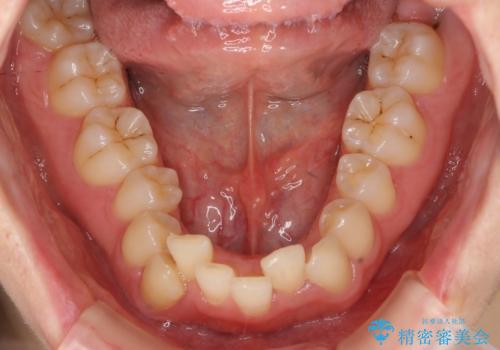

左上5は180度捻転していましたので、そのまま並べています。

遠心移動などは行わず、IPRと拡大のみで治療を行いました。